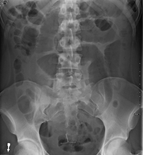

An x-ray of a person with a small bowel volvulus.